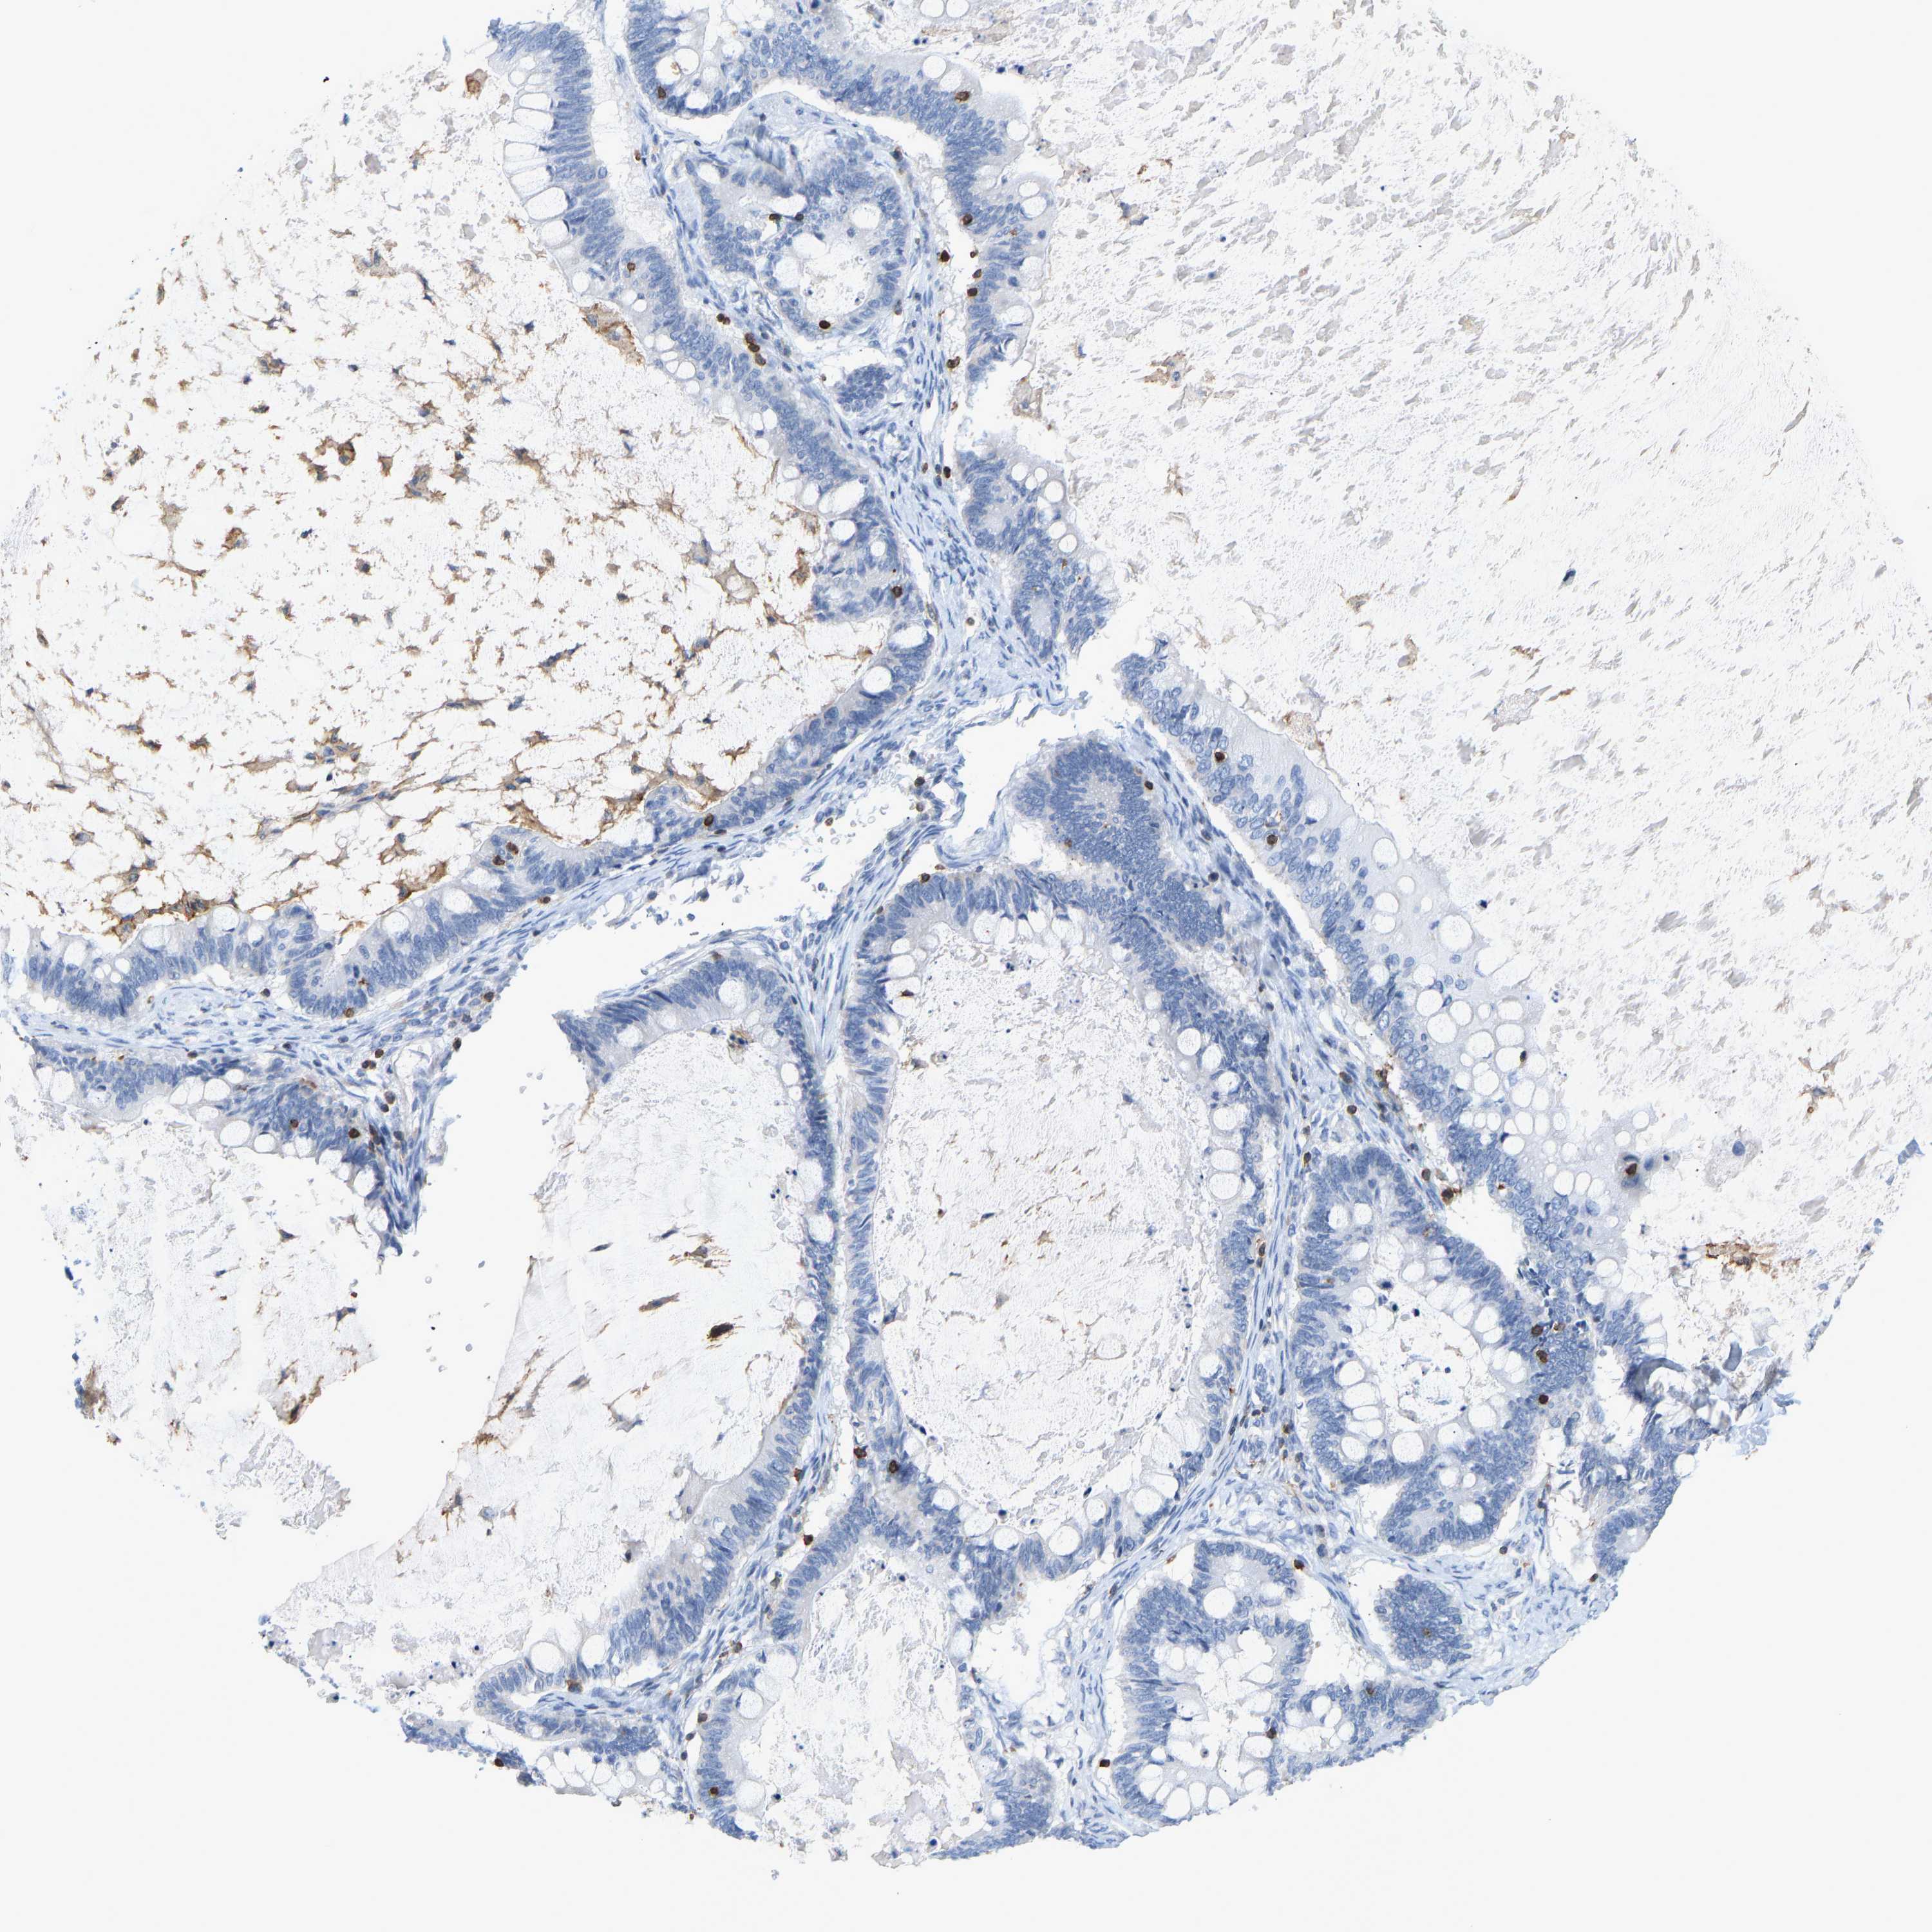

OVARIAN CANCER - Protein expressioni

A mouse-over function shows sample information and annotation data. Click on an image to view it in a full screen mode. Samples can be filtered based on level of antibody staining by selecting one or several of the following categories: high, medium, low and not detected. The assay and annotation is described here.

Note that samples used for immunohistochemistry by the Human Protein Atlas do not correspond to samples in the TCGA dataset.

Antibody stainingi

Antibody staining in the annotated cell types in the current human tissue is reported as not detected, low, medium, or high, based on conventional immunohistochemistry profiling in selected tissues. This score is based on the combination of the staining intensity and fraction of stained cells.

Each image is clickable and will lead to virtual microscopy that enables deeper exploration of all samples and also displays staining intensity scores, fraction scores and subcellular localization as well as patient and tissue information for each sample.

Antibody HPA018849

Antibody HPA019536

Antibody CAB033987

Staining

High

Medium

Low

Not detected

Cystadenocarcinoma, serous, NOS

Carcinoma, endometroid

Cystadenocarcinoma, mucinous, NOS

Carcinoma, NOS